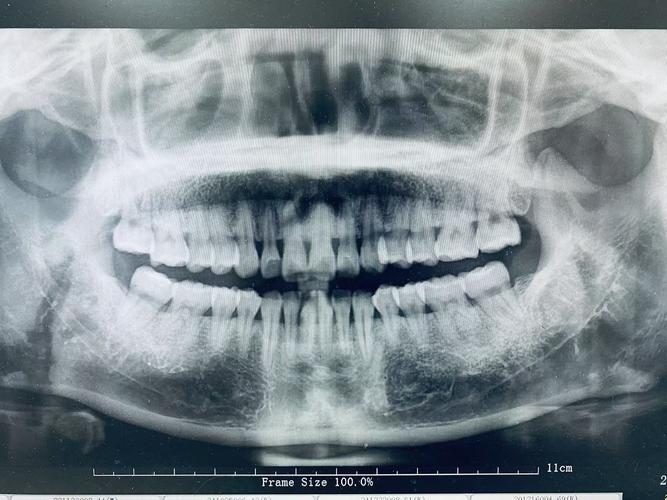

- 全景片(曲面断层片):可全面展示全口牙齿的形态、数量、位置(如埋伏牙、多生牙),牙根长度、弯曲度,以及牙槽骨高度、密度,帮助判断是否存在牙根吸收、骨缺损等问题。